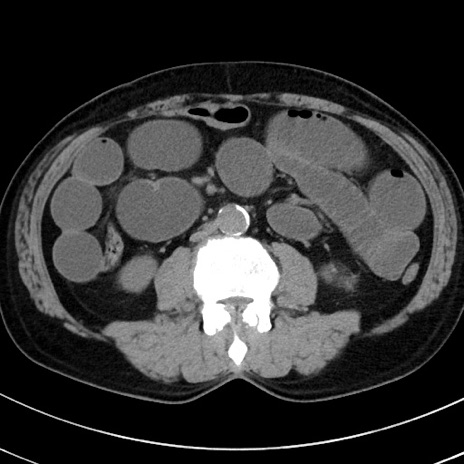

症例38(横断像)

【症例】70歳代 男性

【主訴】腹痛・嘔吐

【現病歴】昨晩より、嘔吐・腹痛あり。今朝になっても嘔吐あり。来院。

【既往歴】心臓バイパス手術、開腹胆摘、腸閉塞

【身体所見】BP 107/71mmHg、HR 116/min、腹部:平坦、軟、下腹部に軽度圧痛あり。反跳痛なし。

【データ】WBC 15100、CRP 0.32